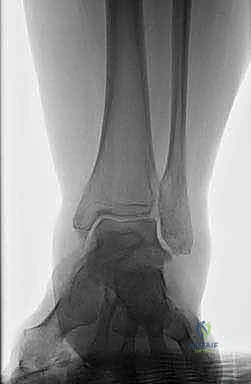

- Initial review of AP and lateral radiographs suggests that talar anatomy is relatively well preserved; however, closer inspection of AP radiograph demonstrates some potential lucency/irregularity in

D E talar body, and lateral radiograph reveals some talar body collapse and subtalar incongruity ( TECH FIG 7B,C ).

CT scan shows fatigue fractures through avascular talar body ( TECH FIG 7D,E ).

TECH FIG 7 • A. Patellar tendon bearing brace. B, C. Preoperative radiographs of patient with talar body avascular necrosis. D, E. CT scan of same patient in A . Note fatigue fractures in the talar body.